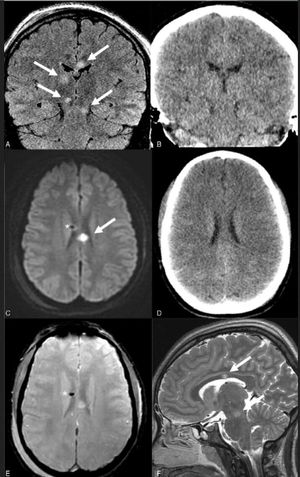

What's your dx? 1. Alzheimer 2. Diffuse axonal disease 3. MS 4. HIV infection of the brain

3. multiple sclerosis. Plaques suggestive of MS are typically found on MRI in the periventricular region, corpus callosum, centrum semiovale, and, to a lesser extent, deep white matter structures and basal ganglia. MS plaques usually have an ovoid appearance.